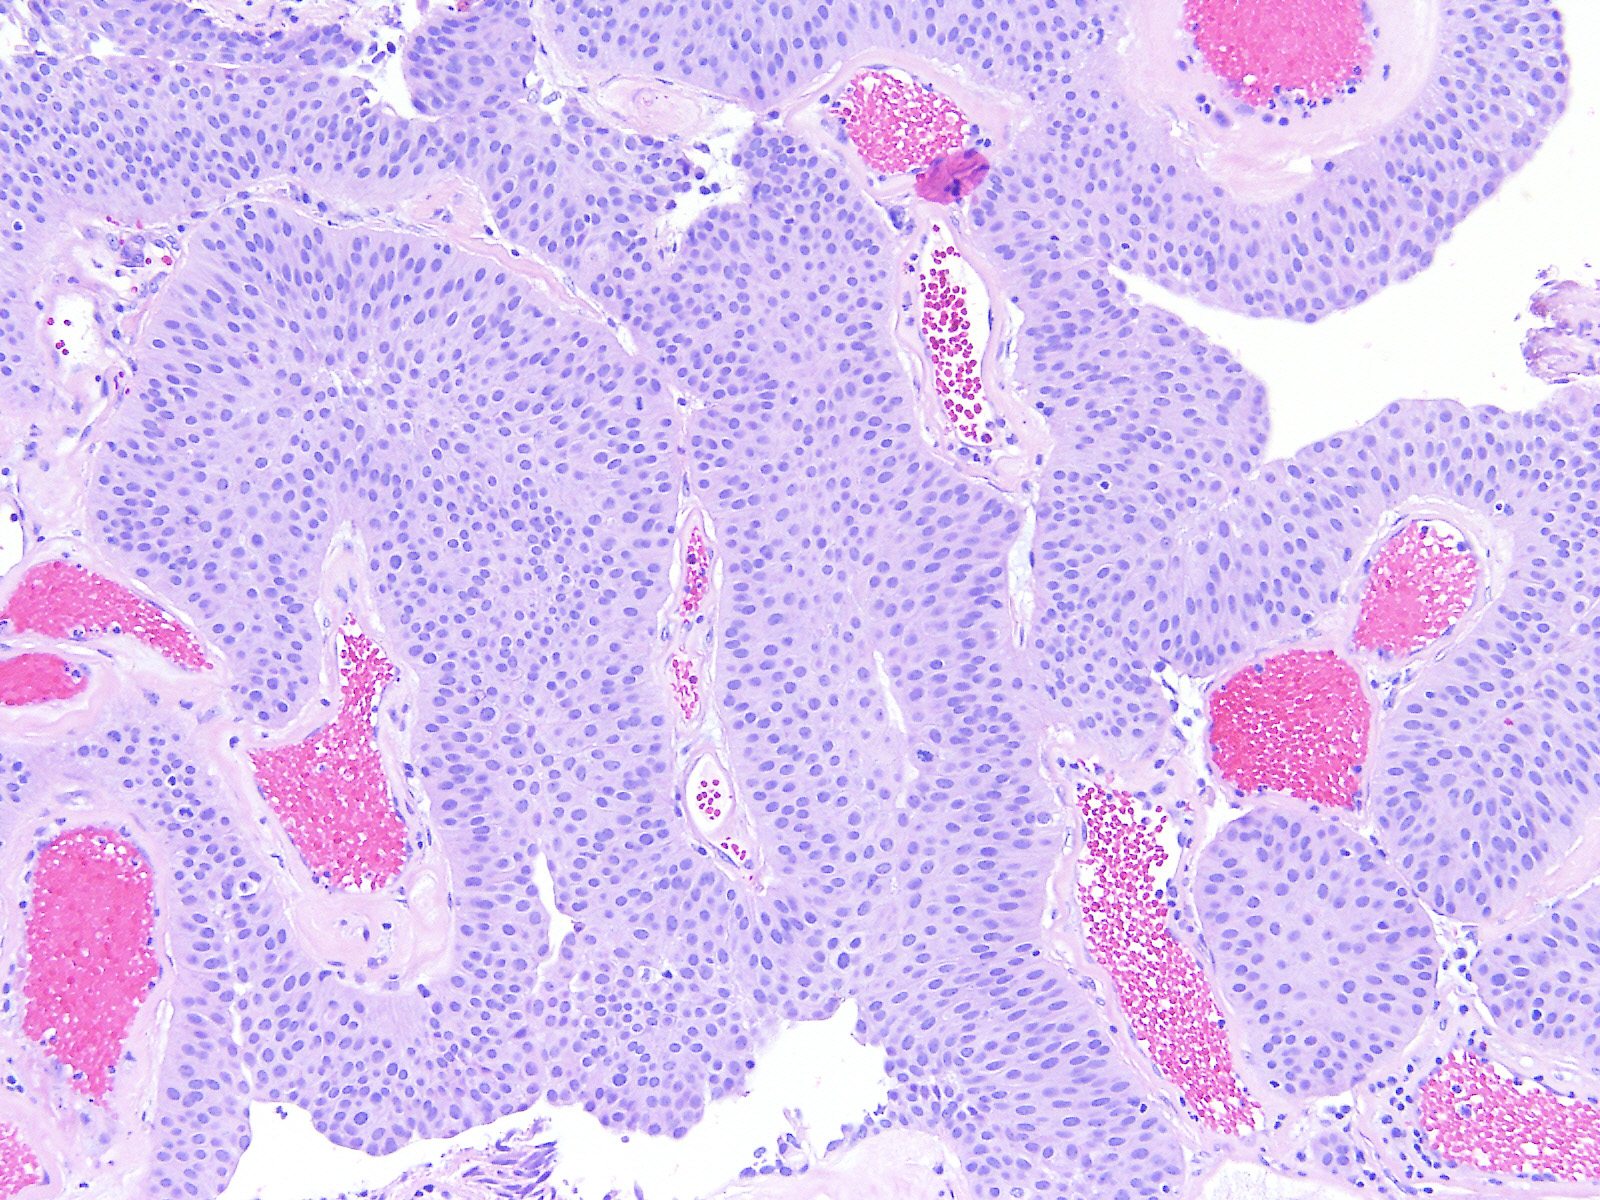

Consensus grade: Low-grade papillary urothelial carcinoma (LG-PUC)

PULMP can be discussed, but mitosis, and I don't like PUNLMPs with mitosis, although in the initail description they have been mentioned |

A 74 year-old woman underwent a TURBT.